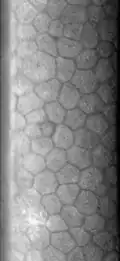

Image de l’endothélium cornéen humain en microscopie spéculaire (cliquer sur l’image pour l’agrandir)

L’endothélium cornéen est une mono-couche cellulaire formant une mosaïque hexagonale. Ses cellules ne se régénèrent pas.

La richesse en protéoglycannes du stroma cornéen provoque un appel d'eau de l'humeur aqueuse vers le stroma qui tend à augmenter son épaisseur, modifiant la courbure et la transparence de la cornée (œdème stromal). Le rôle principal des cellules endothéliales cornéennes est de pomper par transport actif cette eau en excès du stroma vers l'humeur aqueuse afin de maintenir une hydratation constante du stroma compatible avec le rôle physiologique principal de la cornée: la transmission de la lumière. En dessous d'une certaine densité (entre 600 et 800 cellules/mm²), il est admis que le nombre de cellules endothéliales est insuffisant pour assurer un transfert d'eau efficace et l’œdème stromal apparaît.